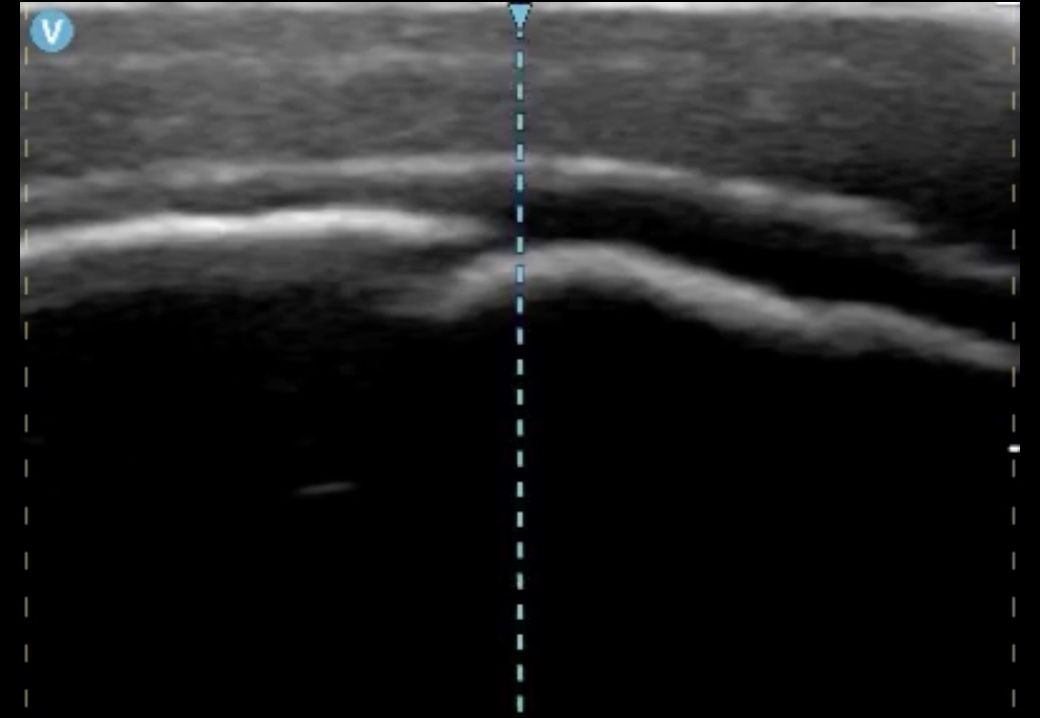

Ante nula mejoría, y retraso considerable en realización de otras pruebas complementarias. Se utiliza sonda lineal de alta frecuencia de ecógrafo portátil para valorar punto de dolor.

Hallazgos ecográficos

En la imagen se observa una disrupción de continuidad cortical ósea con aparente pérdida de esta y con aumento de la ecogenicidad en región perilesional compatible con edema.